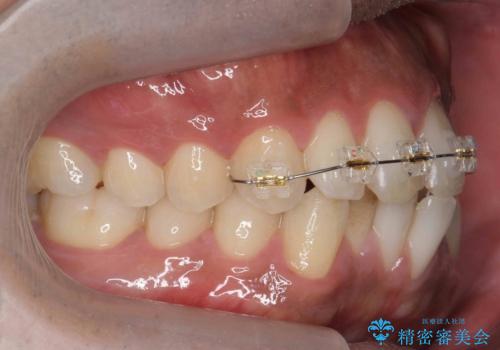

上はワイヤー部分矯正、下はインビザラインの部分矯正コースを行いました。

インビザラインだけでも治療は可能ではあると思いますが、ライトパッケージでは難しいと思います。

また、入れ替えを行う間左上の前歯だけで咬まなくてはならない状況になるため、マウスピース矯正単独で行うと時間がかかり、最悪神経が失活することもありますのでワイヤーがお勧めです。